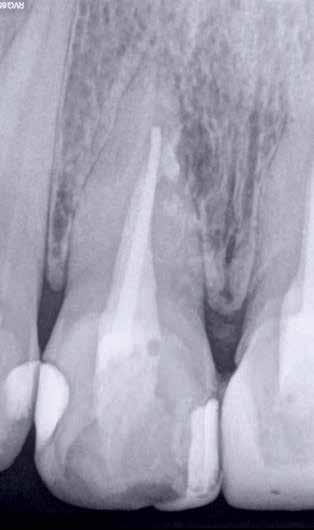

Hölgy páciensem az első konzultáció során tipikus kórtörténetet vázolt fel: Gyermekkora óta szeretett volna fogszabályozó készüléket, hiszen mindig is zavarta a class 2-es eltérésnél tipikusan jellemző nagy overjet (1-3. képek), és természetesen az ezáltal kifelé álló felső metszőfogai, részben a felső metszők protrúziója, részben pedig a disztálisan elhelyezkedő mandibula miatt. Annak ellenére, hogy több fogszabályozó szakorvosnál is járt az évek során, de mivel saggitális eltérése és az alsó metszőfogak torlódása miatt négy kisőrlőfog extrakcióját, illetve emellett sokszor állcsont műtétet is javasoltak neki, nem vágott bele a kezelésbe (4-5. képek).

A fogorvosa – nagyon helyesen – felhívta a figyelmét, hogy parodontális státusza is valószínűsíthetően romlani fog az eltérése miatt, újabb kört futott, immár 39 évesen, de még mindig premoláris fogak húzása és állcsontműtét nélkül szerette volna a fogszabályozást.

A konzultáció során arról is beszéltünk – ahogy az ilyenkor lenni szokott –, sohasem szeretett igazán mosolyogni, de a Pitts Protokolloknak köszönhetően az arc- és mosolyesztétikai céloknak megfelelően kerül megvalósításra az okklúziós korrekció. Az okklúziós kezelési célok az alábbiak voltak: a felső és alsó fogív nivellálása és tágítása, az alsó fogsor/ mandibula mezializálása, valamint a harapás megemelése által a mélyharapás rendezése.

Az esztétikai kezelési céloknál a Pitts elvek szerint a legfontosabb fogak a felső, középső metszők, a cél ezeknek a tökéletes pozícióba állítása. A legfontosabb, hogy a felső, középső metszők labiális felszíne merőleges legyen a Frankfurti Horizontálisra, vagyis természetes fejtartásnál (Natural Head Position) párhuzamos legyen a vertikális síkkal (6. kép) Ehhez az ideális pozícióhoz képest minél protrudáltabbak a felső metszők, annál laposabb, szemből nézve kevésbé ívesebb lesz a mosolyvonal, másrészt optikailag a metszők

hossza is rövidül, azaz a Vertical Incisor Display (Metszőfog láthatóság) csökken. A miniesztétikai, vagyis a mosolyesztétikai eredmény szempontjából egyik jelenség sem kívánatos. A mikroesztétika (a fog- és ínyesztétika) is szorosan hozzátartozik az esztétikai paraméterekhez, ennek tökéletesítése is minden esetben a célok közé tartozik fogkontúrálással vagy esztétikai fogászati felépítéssel, továbbá interproximális redukcióval és szükség esetén lézeres ínykontúrálással (7. kép).

A kezelést Pitts-21-es fogszabályozó készülék alkalmazásával végeztük el. A felső fogíven mosolyvonal beállító esztétikai (Smile Arc Protection - SAP), az alsó fogíven a Spee görbe kiegyenlítését szolgáló funkcionális bracket pozicionálást

alkalmaztunk. Előbbi elengedhetetlen a szép, íves mosolyvonal kialakításához, utóbbi pedig az alsó fogsor mezializálásához, és így az első osztályú sagittális okklúzió kialakításához. Az alsó metszők torlódásának feloldására tolórugókat alkalmaztunk az első hónapban (8. kép)

A protokollok szerves része a mesterséges harapásemelés, melynek segítségével – mintegy kivéve a rágóerők fogmozgatásokat akadályozó hatását – segítjük fogszabályozó rendszer működését. Ezek a ragasztásnál az alsó 7-esekre, majd később a felső 4-esekre kerültek (9. kép).

A harapást beállító elasztikus gumihúzásokat, mint minden kezelésnél, ebben az esetben is folyamatosan, az egész ke-

zelés alatt 24 órában (étkezések kivételével) viselte a páciens. Segítségükkel történt az alsó fogsor mezializálása, és a harapásemelésben is fontos a szerepük a disztálharapás korrekciója során. Az utolsó hónapokban az okklúziós finomítások is részben a segítségükkel történnek az ívhajlítások mellett (10. kép).

A fogkontúrálás és az interproximális redukció alkalmazásával a mikroesztétikai részletek tökéletesítése is megtörtént (11. kép) A kezelés mindössze 16 hónapig tartott, megtörtént a rágófunkció helyreállítása, és az esztétikai végeredmény sokéves várakozás után valóban fordulópontot jelentett páciensünk életében (12-14. képek).